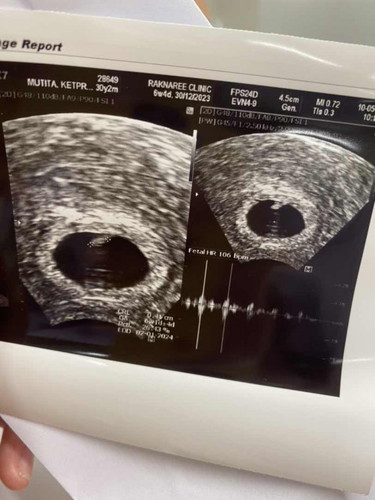

ท้อง 6 week แม่ๆถือเรื่องการบอกคนอื่นก่อน 3 เดือนมั้ยคะ

ตอนนี้ท้อง 6 week ค่ะ อยากบออกคนรอบข้างเพื่อจะได้ปรับตัวถูกเวลาชวนไปไหนมาไหน แต่บางคนก็บอกว่าอย่าพึ่งบอกใครถือเคล็ดรอ 3 เดือนก่อน